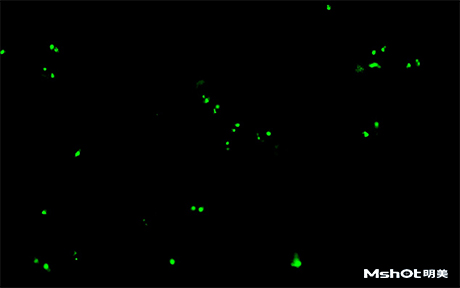

北京某试剂单位已有一台奥林巴斯生物显微镜BX61,希望能进行CTC检测,在电脑中成像拍摄保存图片,刚好我们在北京有办事处,工程师了解到具体需求分析后提供一款明美数字摄像头MS23,搭配奥林巴斯BX61生物显微镜在40X观察下,效果如图: